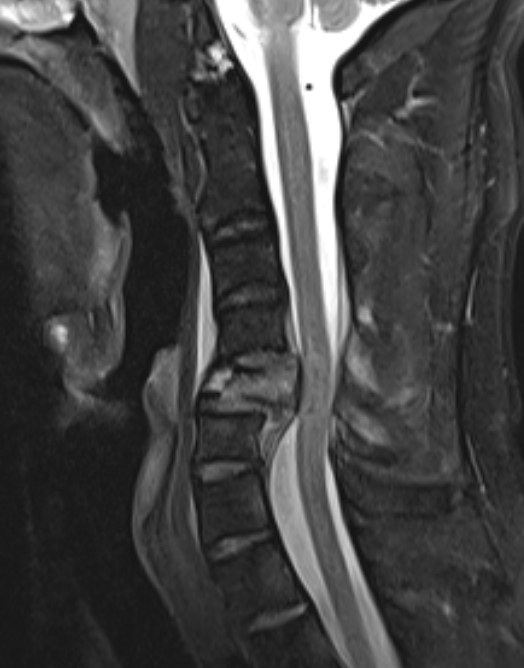

MRI

Assess integrity of posterior column

Evaluate cord injury

MRI images demonstrating spinal cord injury and posterior ligamentous injury